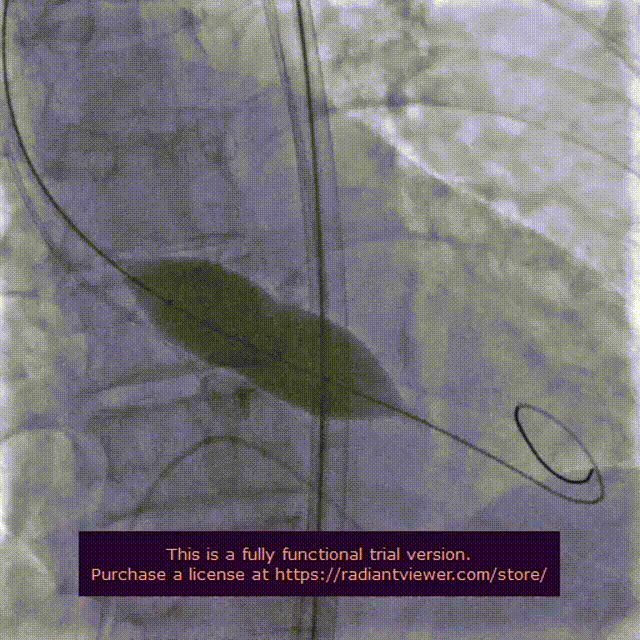

22 mm球囊预扩张

输送系统定位

VenusA-Plus®释放过程

瓣膜完整形态